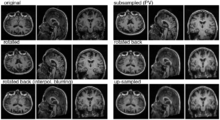

Experiment 1: Anisotropy degenerates Joint Histogram & Global Optimum

• Rationale: This experiment produces directly joint histograms and difference(ratio) images w/o the need to run the actual registration, i.e. we compare the effects of voxel anisotropy on the theoretical optimum: Move, filter and subsample identical image pair, then resample back to original position and build joint histograms and subtraction images. Because of the increasing PV effects we expect to see a degenerating joint histogram and a subtraction image with increasing edge artifacts. We can then try to interpret how the optimizer will behave in this environment. The benefit of this metric is that we circumvent the stochastic nature of the registration output.

• Pipeline

1. original

2. move by known amount (Aff0)

3. PV filter blur + subsample to anisotropic voxel size

4. rotate back (inv(Aff0))

5. upsample to original size

6. compute joint histogram

7. evaluate relative blurring: deviation from unity line

• Results

• Discussion

• need an intuitive way or metric to interpret the blurring of the JH, what it means in terms of registration accuracy, robustness, capture range etc. One way would be to quantify the off-diagnoal amount of intensity, another more visual to compare to blurring from misalignment, i.e. find the misalignment that produces a similarly blurred JH.

• the blurred histogram represents the new practically achievable global optimum, relative to the theoretical ideal of a 45-degree unity line

• the partial volume "bleed" works relative to the histogram mode/mean, i.e. low intensities are more likely to get brighter by PV, whereas higher intensities are more likely to be surrounded by lower ones and hence become darker by PV. Thus the joint histogram gets "squished" toward the middle from both ends (Fig.1), and ends up with a rotation relative to the 45 axis around a midpoint that's somewhere near the mode or mean intensity. We could measure this rotation as another metric. Most straightforward would be via principal axes.